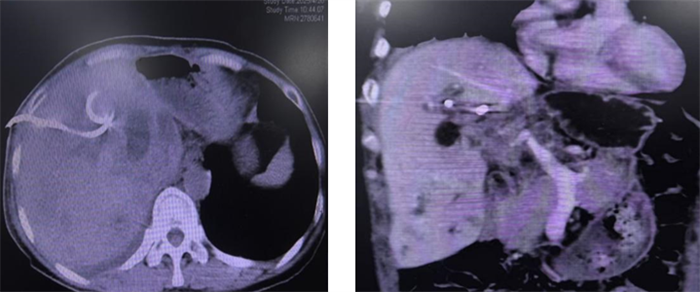

术后复查CT:支架植入术后,肝内胆管扩张较前明显好转